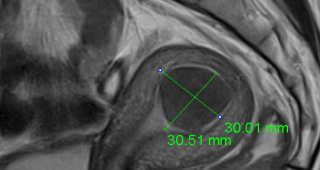

자궁선근증 비수술 하이푸 치료 후 임신사례입니다.하이푸 시술전 MRI 사진상 자궁은 6cm 크기로 심하게 후굴되어 있으며 자궁후벽을 중심으로 자궁선근증변화 소견이 관찰됩니다. 아래의 MRI 사진은 자궁선근증 하이푸...